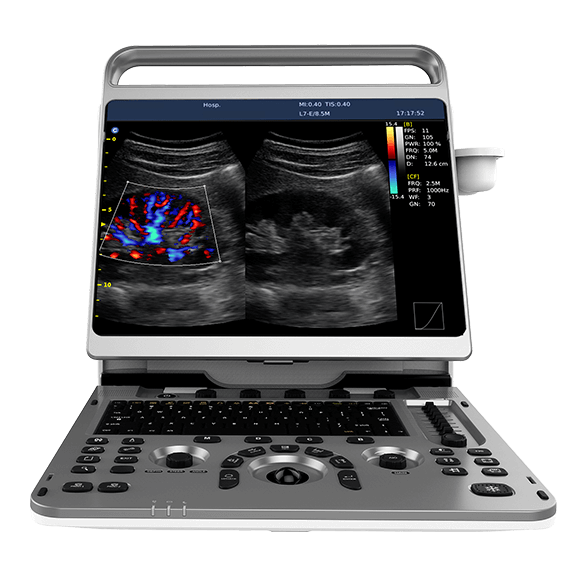

The EBit provides all the power you need for today?s challenging clinical environment, yet remain ultra-portable, ultra-affordable.

The EBit provides all the power you need for today?s challenging clinical environment, yet remain ultra-portable, ultra-affordable. With it?s cutting-edge imaging technologies, precise and intuitive workflow, ergonomic and eco-friendly design, versatile transducers for all applications from top to toe, we firmly believe the EBit to be the very best portable ultrasound in its class today.